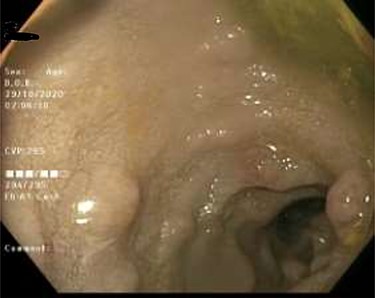

As work up for his abdominal pain and anemia he underwent gastroscopy on 29 October 2020 that revealed congested and nodular gastric mucosa (mass-like) and at lesser extend in the first and second part of duodenum (Figs 1 and 2). Biopsies were taken from the gastric lesion and duodenum. Histopathological findings from gastric mass and duodenum showed marked stromal hyalinosis, which appeared as a cellular pink material on H&E stain (Figs 3 and 5). Congo red stain (amyloid stain) showed apple green birefringence under polarized light on both gastric and duodenal biopsies (Figs 4 and 6).

Gastric mucosa seen by endoscopy as nodular, prominent and congested.

Duodenal mucosa seen by endoscopy shows some erythema and nodularity.